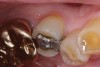

Replacement of existing restorations is responsible for 75% of all operative dentistry.15,19 The reasons for placement and replacement of restorations of direct restorative materials include: primary caries (Figure 1 and Figure 2); recurrent caries (Figure 3); poor margins (Figure 4 and Figure 5); restoration fracture (Figure 6 and Figure 7); tooth fracture (Figure 8); esthetics (Figure 9); non-carious tooth structure lost (attrition, abrasion, abfraction, erosion) (Figure 10); and pain/sensitivity.

Fig. 4 Defective margins. Mandibular first molar with an amalgam restoration with defective margins.

Figure 4  Defective margins. Mandibular first molar with an amalgam restoration with defective margins.

Figure 4